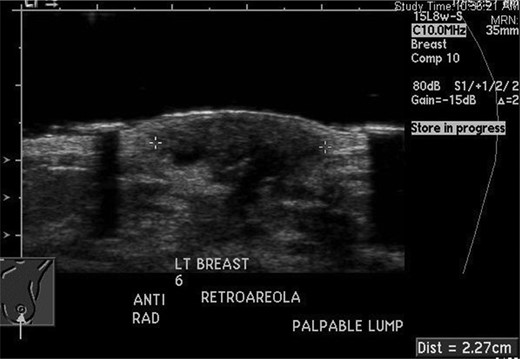

The excisional biopsy was performed in June 2012, which revealed a diagnosis of leiomyosarcoma (slides seen in Figs. 3–5).

Cross section at low power. Intersecting bundles. Multinucleated giant cell in the bottom right.